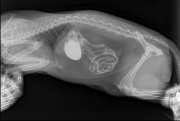

Простите, не удержалась :-) Ещё зимой внезапно оказалось, что детонька стала бояться переноски и фиг ты её поймаешь, чтобы туда посадить. Нынешняя эпическая битва Большого Бегемота с котэ проходила с переменным перевесом сторон, при этом в процессе оказались дважды засранными ...